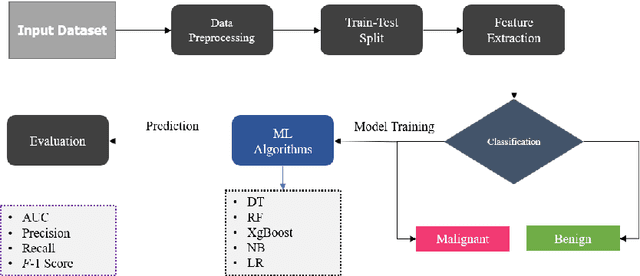

Nowadays, Breast cancer has risen to become one of the most prominent causes of death in recent years. Among all malignancies, this is the most frequent and the major cause of death for women globally. Manually diagnosing this disease requires a good amount of time and expertise. Breast cancer detection is time-consuming, and the spread of the disease can be reduced by developing machine-based breast cancer predictions. In Machine learning, the system can learn from prior instances and find hard-to-detect patterns from noisy or complicated data sets using various statistical, probabilistic, and optimization approaches. This work compares several machine learning algorithm's classification accuracy, precision, sensitivity, and specificity on a newly collected dataset. In this work Decision tree, Random Forest, Logistic Regression, Naive Bayes, and XGBoost, these five machine learning approaches have been implemented to get the best performance on our dataset. This study focuses on finding the best algorithm that can forecast breast cancer with maximum accuracy in terms of its classes. This work evaluated the quality of each algorithm's data classification in terms of efficiency and effectiveness. And also compared with other published work on this domain. After implementing the model, this study achieved the best model accuracy, 94% on Random Forest and XGBoost.